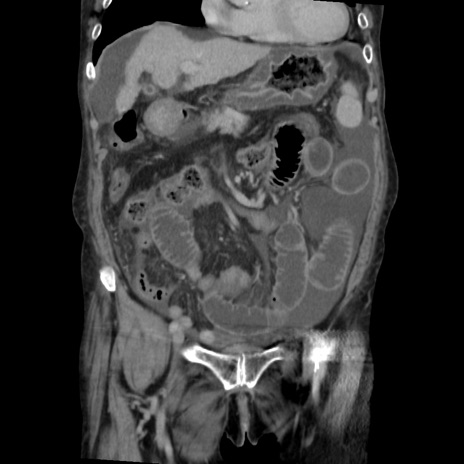

症例31(冠状断像)

【症例】80歳代 女性

【主訴】腹部膨満感

【現病歴】他院にて肝硬変にてフォロー中。1週間前から便秘、腹部膨満感、臍部腫瘤あり受診となる。

【既往歴】肝硬変

【身体所見】腹部膨隆あり、皮膚変化なし、疼痛なし。

【データ】WBC 4600、CRP 0.25